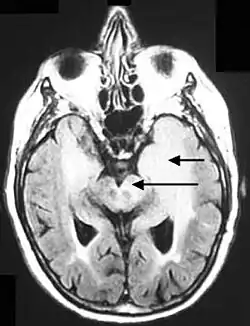

Axial fluid-attenuated inversion recovery MRI image demonstrating tumor-related infiltration involving lenticular nuclei (Arrow). -

Axial fluid-attenuated inversion recovery MRI image demonstrating tumor-related infiltration involving both temporal lobes (Short arrow), and the substantia nigra (Long arrow).